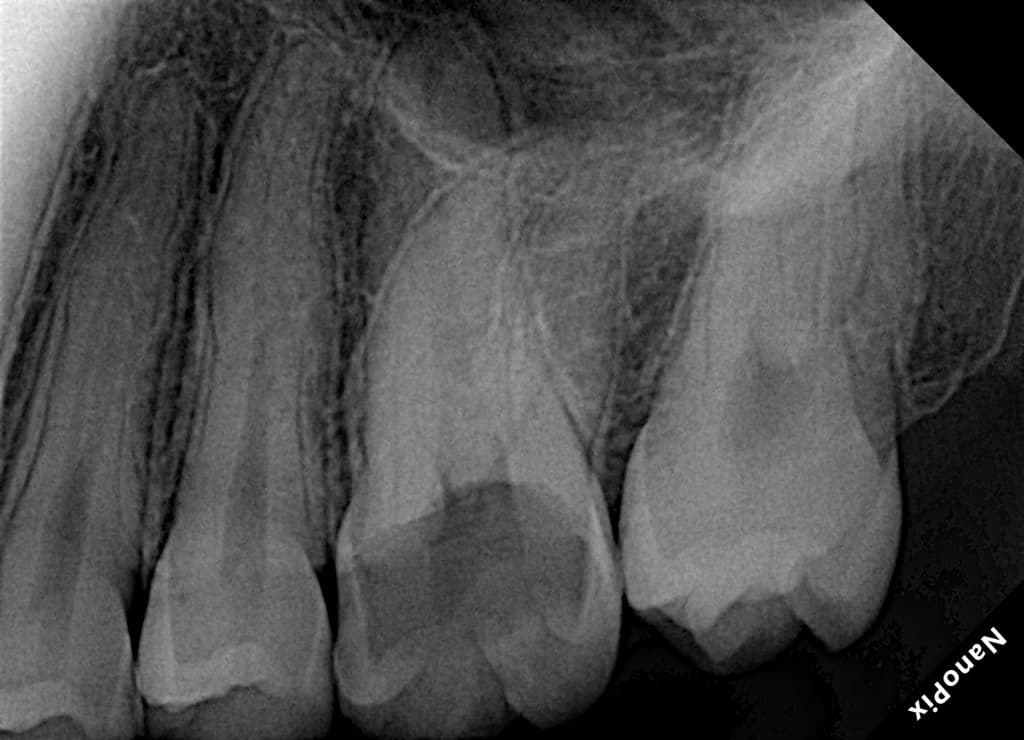

UL6 with SAP and deep palatal caries.

Caries removal and cleaning to determine the margin height then margin elevation as a pre endo build up under rubber dam isolation, endodontic treatment in the same visit to minimize flar up and direct restoration was done in the second visit.